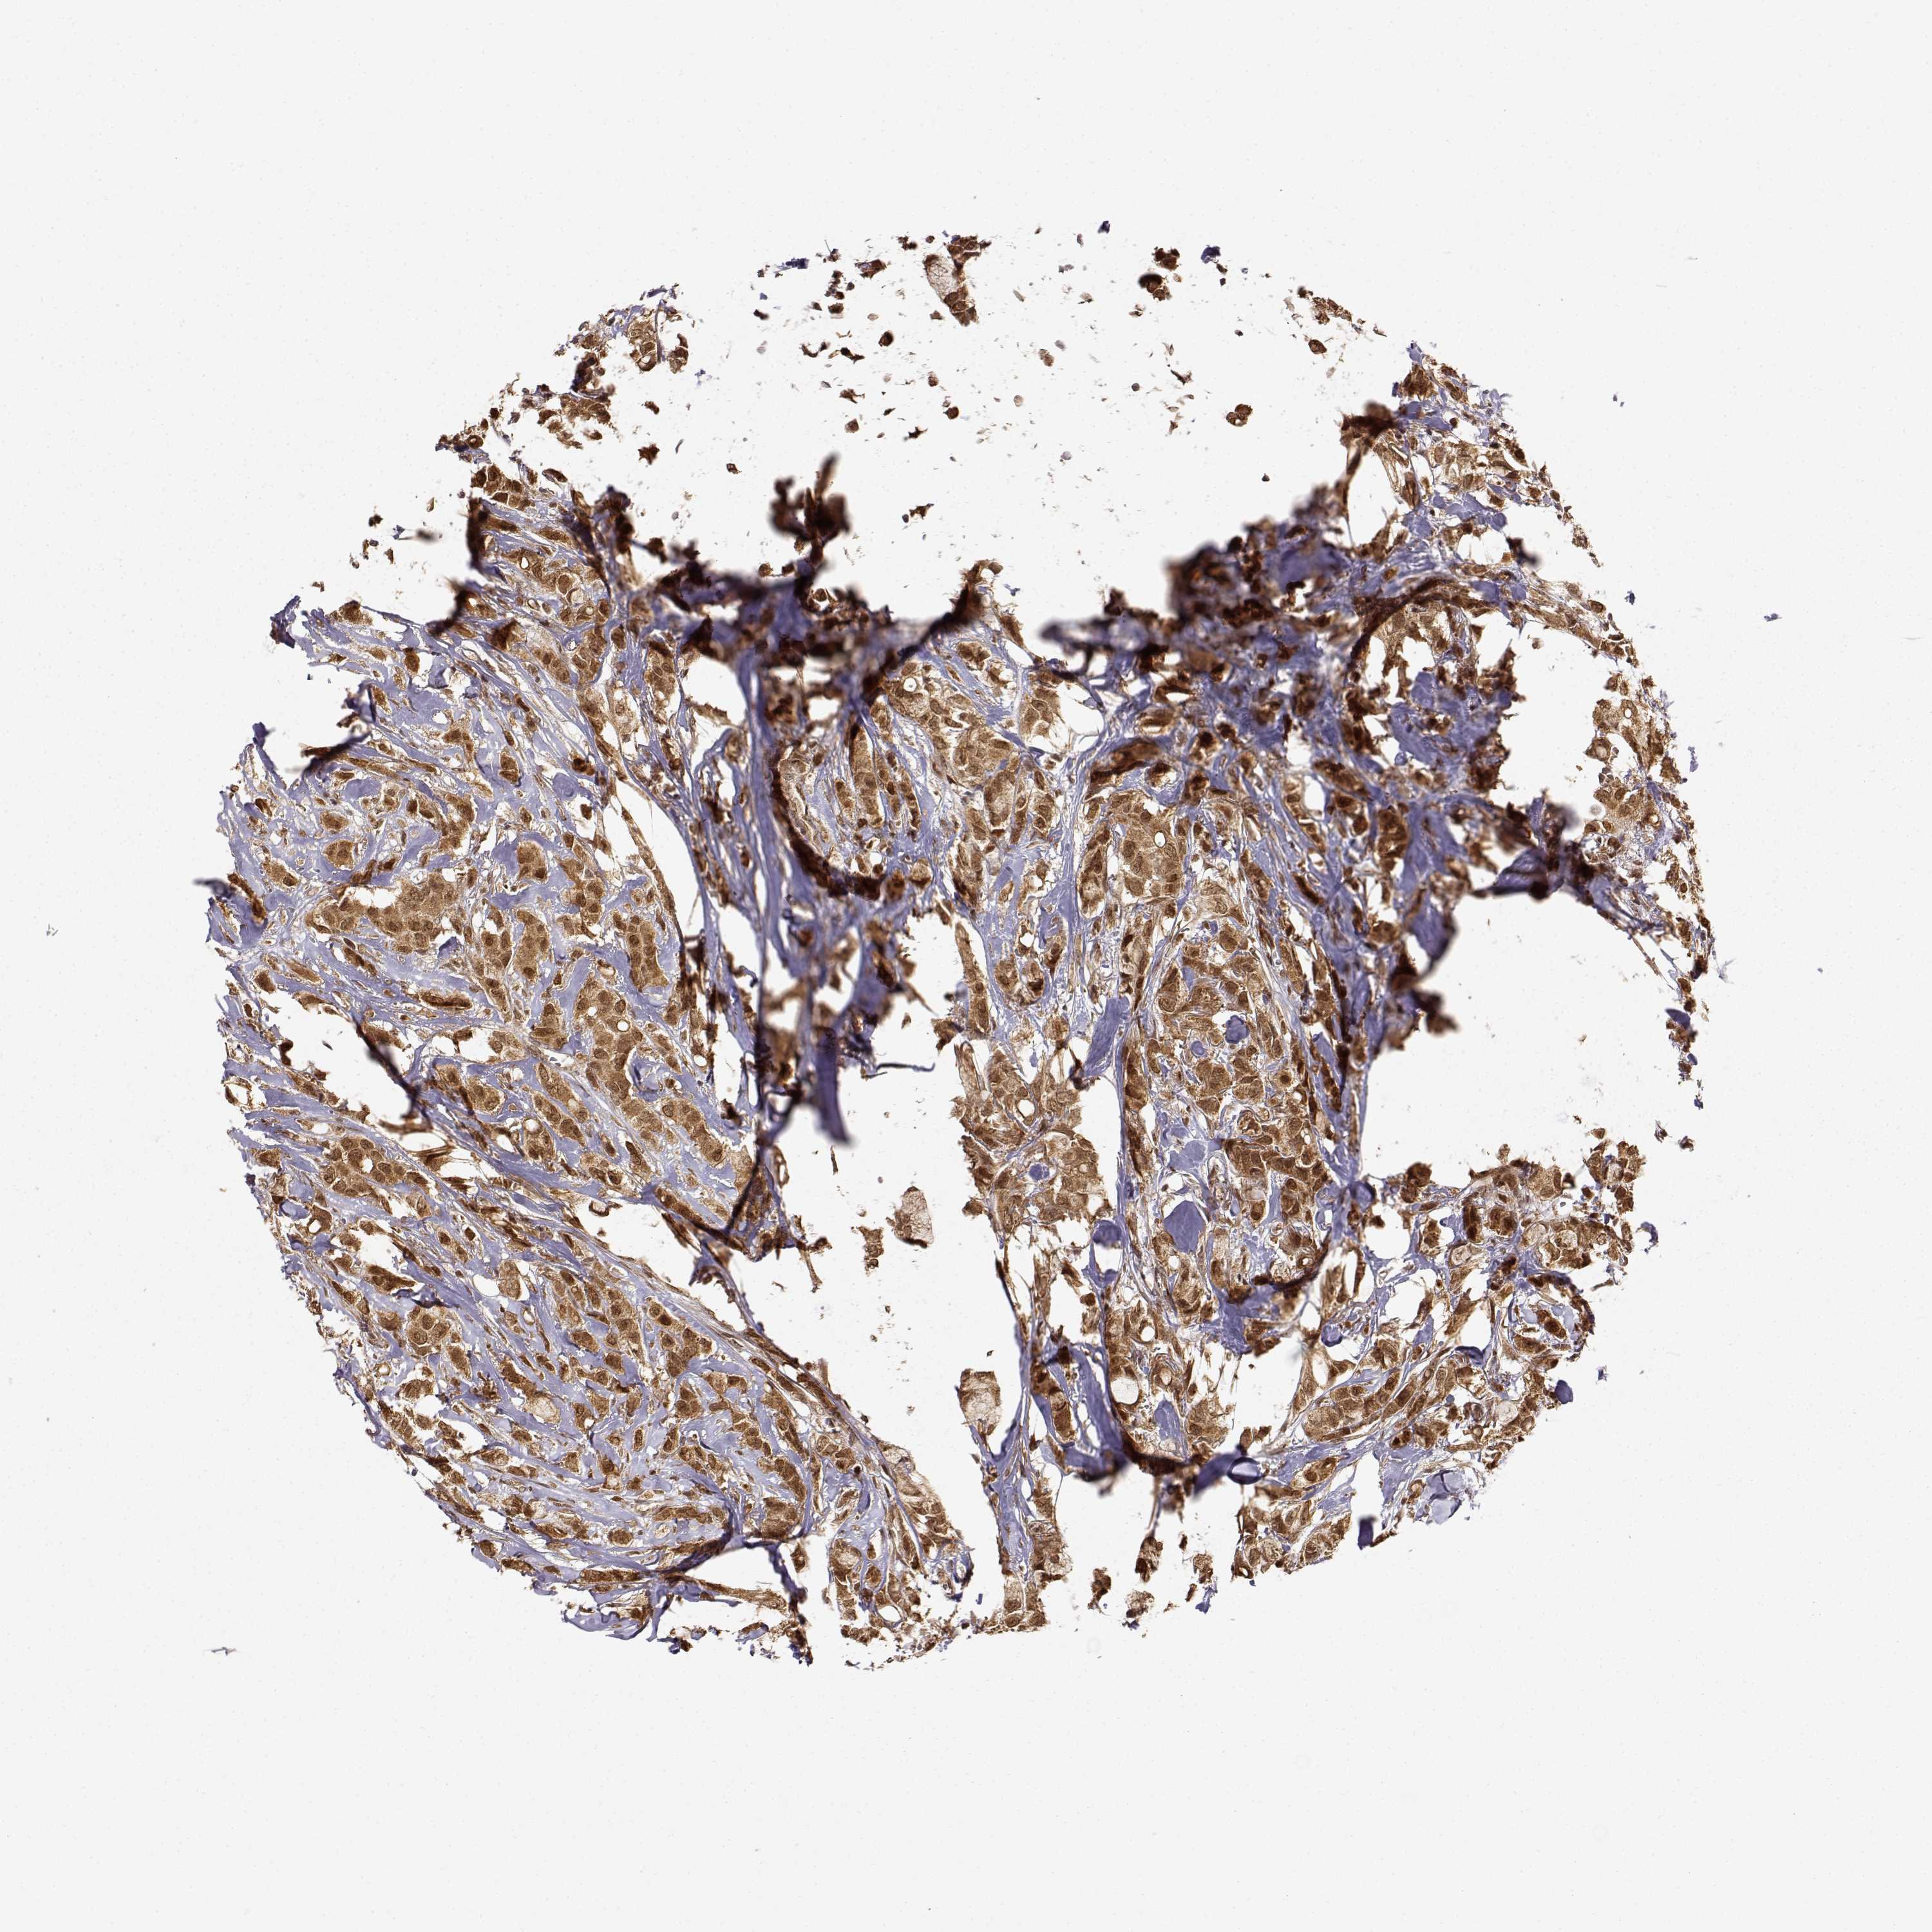

CANCER BREAST CANCER Show tissue menu

BRCA TCGA BRCA VALIDATION PROTEIN EXPRESSION